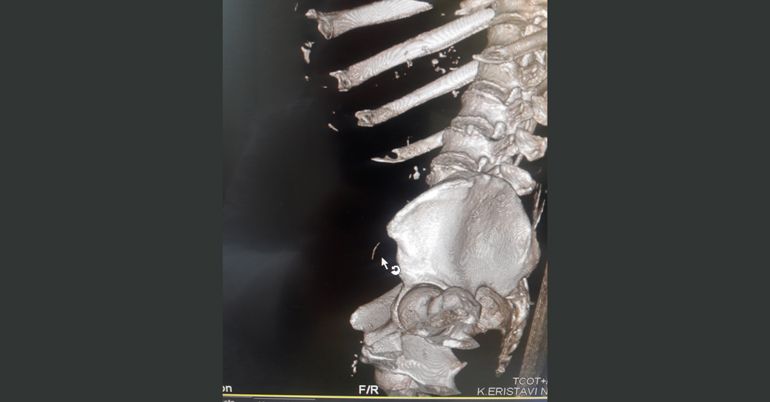

კლინიკის რადიოლოგმა ირაკლი გიგიაძემ შენიშნა, რომ წვრილი ნაწლავი უცხო სხეულით იყო დაზიანებული. დაუდგენელი სახეობის უცხო სხეული ნაწლავის სანათურიდან მუცლის ღრუში გამოდიოდა. პაციენტს ჩაუტარდა ლაპარასკოპია. მოიძებნა და ამოღებულ იქნა უცხო სხეული, ხოლო წვრილი ნაწლავის დაზიანებული უბანი გაიკერა.

უცხო სხეული, რომელიც ქირურგებმა პაციენტის წვრილი ნაწლავიდან ამოიღეს, აღმოჩნდა მეტალის მავთული (ჭურჭლის სახეხის შემადგენელი ნაწილი), რომლის ზომაც 4 სმ–ს შეადგენდა და კუჭ–ნაწლავში საკვებიდან მოხვდა.